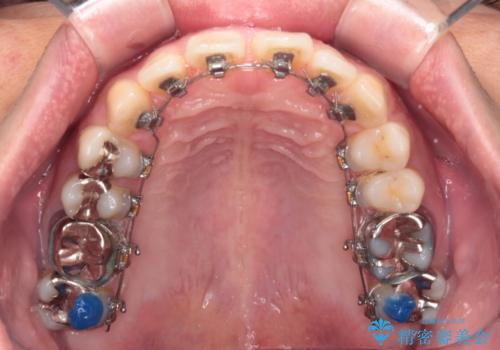

深い咬み合わせと前歯の隙間 ハーフリンガルによる矯正治療

- 矯正装置

- ハーフリンガル

- 咬み合わせにより上顎正中に隙間ができているとのことで来院された患者様です。

インビザラインは自己管理が煩わしく、表側のワイヤー装置は目立つので避けたいとのことで、上顎だけが裏側装置のハーフリンガルにて矯正治療を行うこととしました。